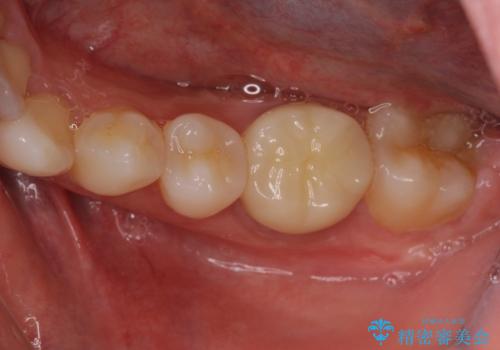

海外転勤が決まり、急いでセラミック治療をしてほしいとご来院された患者様です。

根管治療に症状がなく、上の歯に関しては土台もそのまま使用可能であったため、下の歯の土台、上下の歯のセラミック治療を行いました。

今回は幸い、症状がなく、根管治療の再治療が必要でないため、円滑に治療を進めることができました。